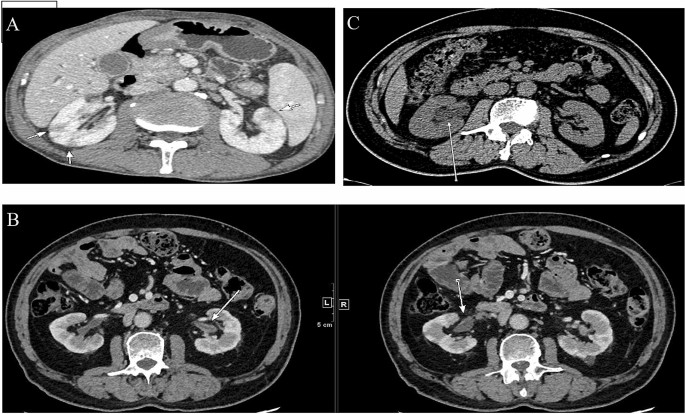

Radiological findings

We used contrast-enhanced CT to identify radiological abnormalities in IgG4-RKD+ patients except those with renal dysfunction. Fifty of the 53 IgG4-RKD+ patients exhibited characteristic findings of the kidney radiology. Among them, 14 patients were presented with more than one kind of lesion. The most common finding is multiple, often bilateral, hypodense lesions in 31 (58.5%) IgG4-RKD+ patients, which are called small cortical hypodense nodules (Fig. 4A), followed by thickening of the renal pelvic wall in 18 (34.0%) IgG4-RKD+ patients (Fig. 4B), and ureteric obstruction and hydronephrosis related to RPF in 9 (17.0%) patients who had also other specific kidney lesions of IgG4-RKD+ (Fig. 4C). Besides, diffuse patchy involvement, tumor-like less-enhanced mass and rim-like lesion were observed in 8 (15.1%), 2 (3.8%) and 1(1.9%) patient, respectively.

Main abnormalities on renal imaging were revealed in a total of 42 (79.2%) of IgG4-RKD+ patients: multiple low-density nodules, hydronephrosis and thickening of renal pelvic wall. Similar with previous studies, there were also some other imaging manifestations in our cohort, including diffuse patchy involvement of the bilateral kidneys and rim-like lesion of the kidney11,22. CT was the most common mode of renal imaging, including PET-CT, which is increasingly used. PET-CT could contribute to excluding malignancy with little radiative damage. Moreover, PET-CT is helpful for discovering the involvement of some silent lesions, however, its cost should also be taken into account.